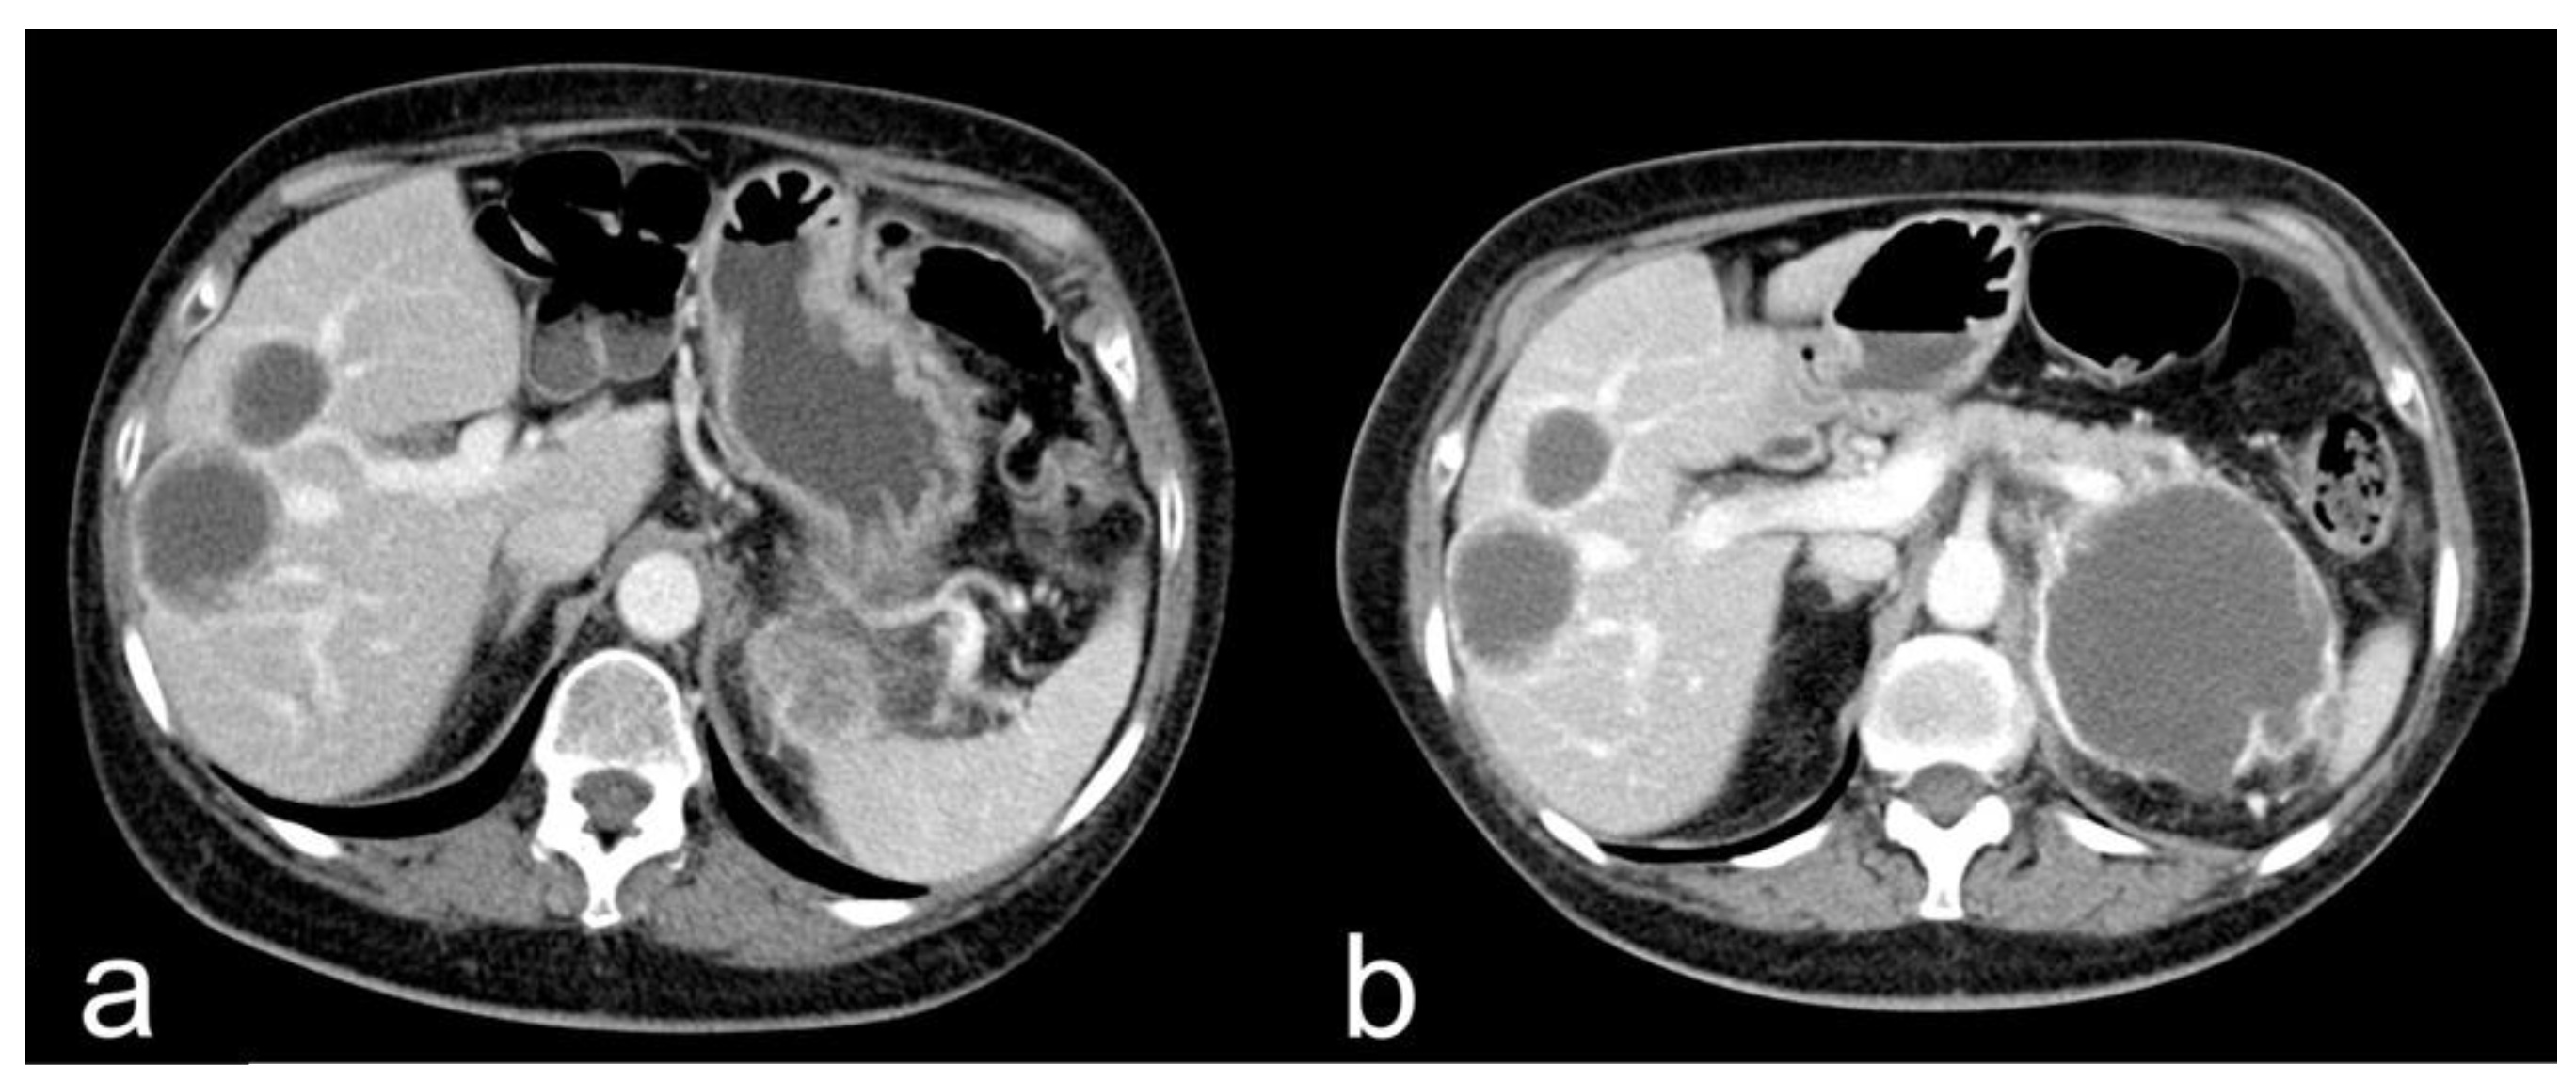

- Complete response (CR): disappearance of all target lesions together with any pathological lymph nodes (target or non-target) with short axis < 10 mm (Figure 1).